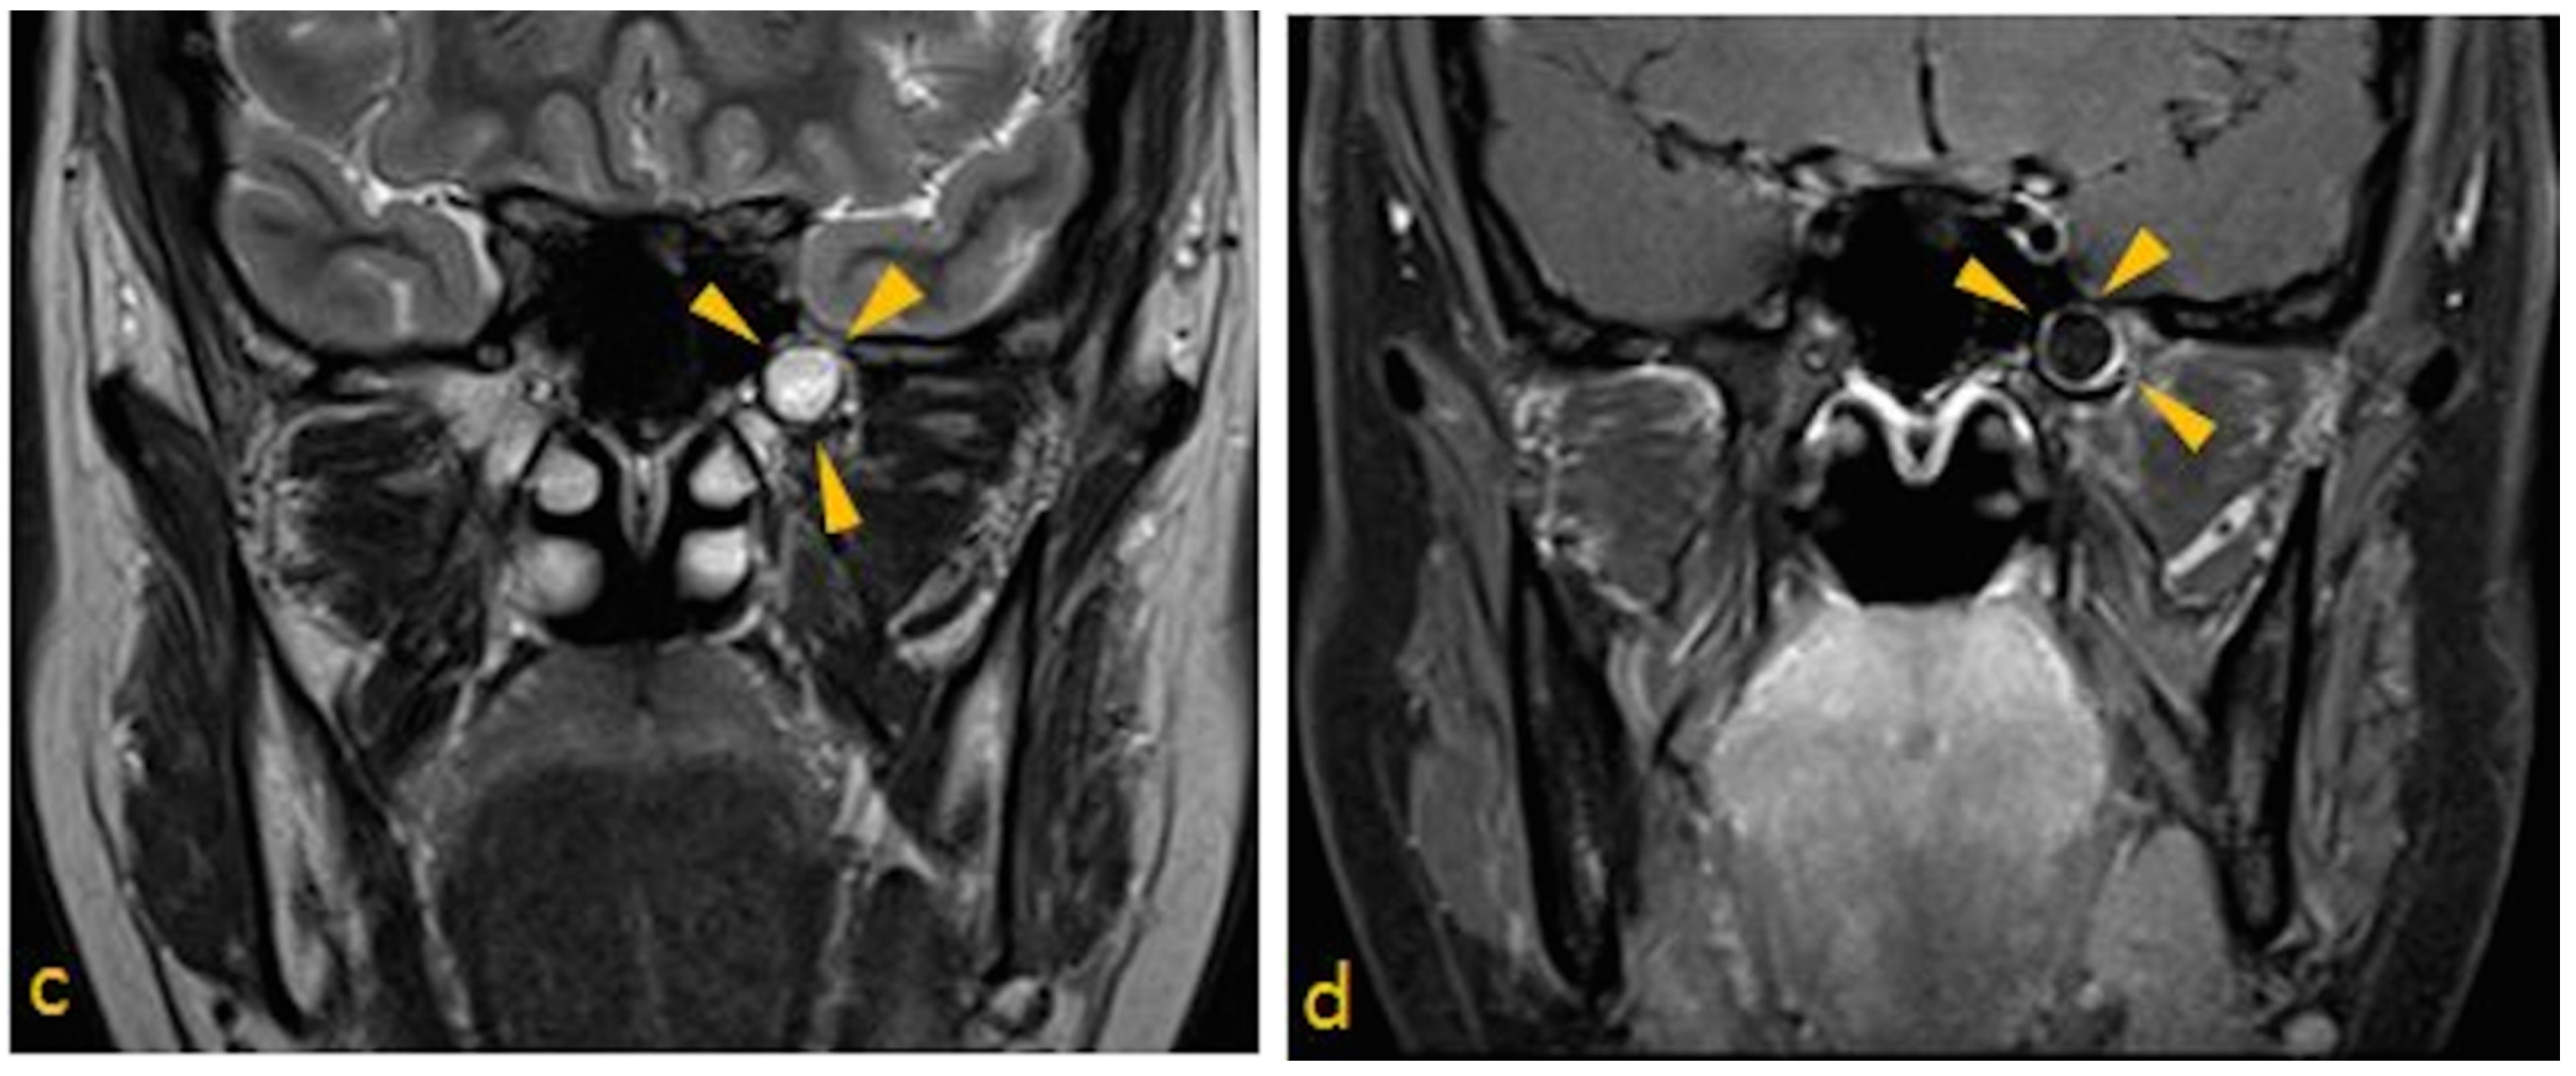

- Lesion must be non-expansile with sclerotic, well-defined margin, and should be located at a site of normal pneumatization. Evidence of fatty content should be present. Internal curvilinear calcifications should be noted on CT images [1].

- Since, sphenoid sinus is closely related to several vital neurovascular structures such as internal carotid artery and optic nerve, any associated skull-base foramina should remain intact and patent.